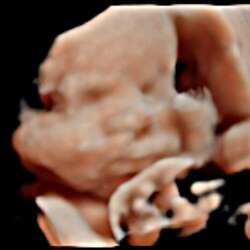

Ik helaas ook. 1e keer was spontane abortus, 2e keer een missed abortion... Tussendoor gelukkig wel een gezond kindje op de wereld morgen zetten. Dus houd hoop iedereen! Ik ben nu bijna 35, maar hoop echt dat er ons meisje een broertje of zusje kunnen geven...

In oktober ons kindje met 15 weken zwangerschap verloren. Ook het gedichtje oneindig vind ik heel erg mooi. Misschien hebben jullie er ook wat aan. Dikke knuffel voor iedereen die het moeilijk heeft.